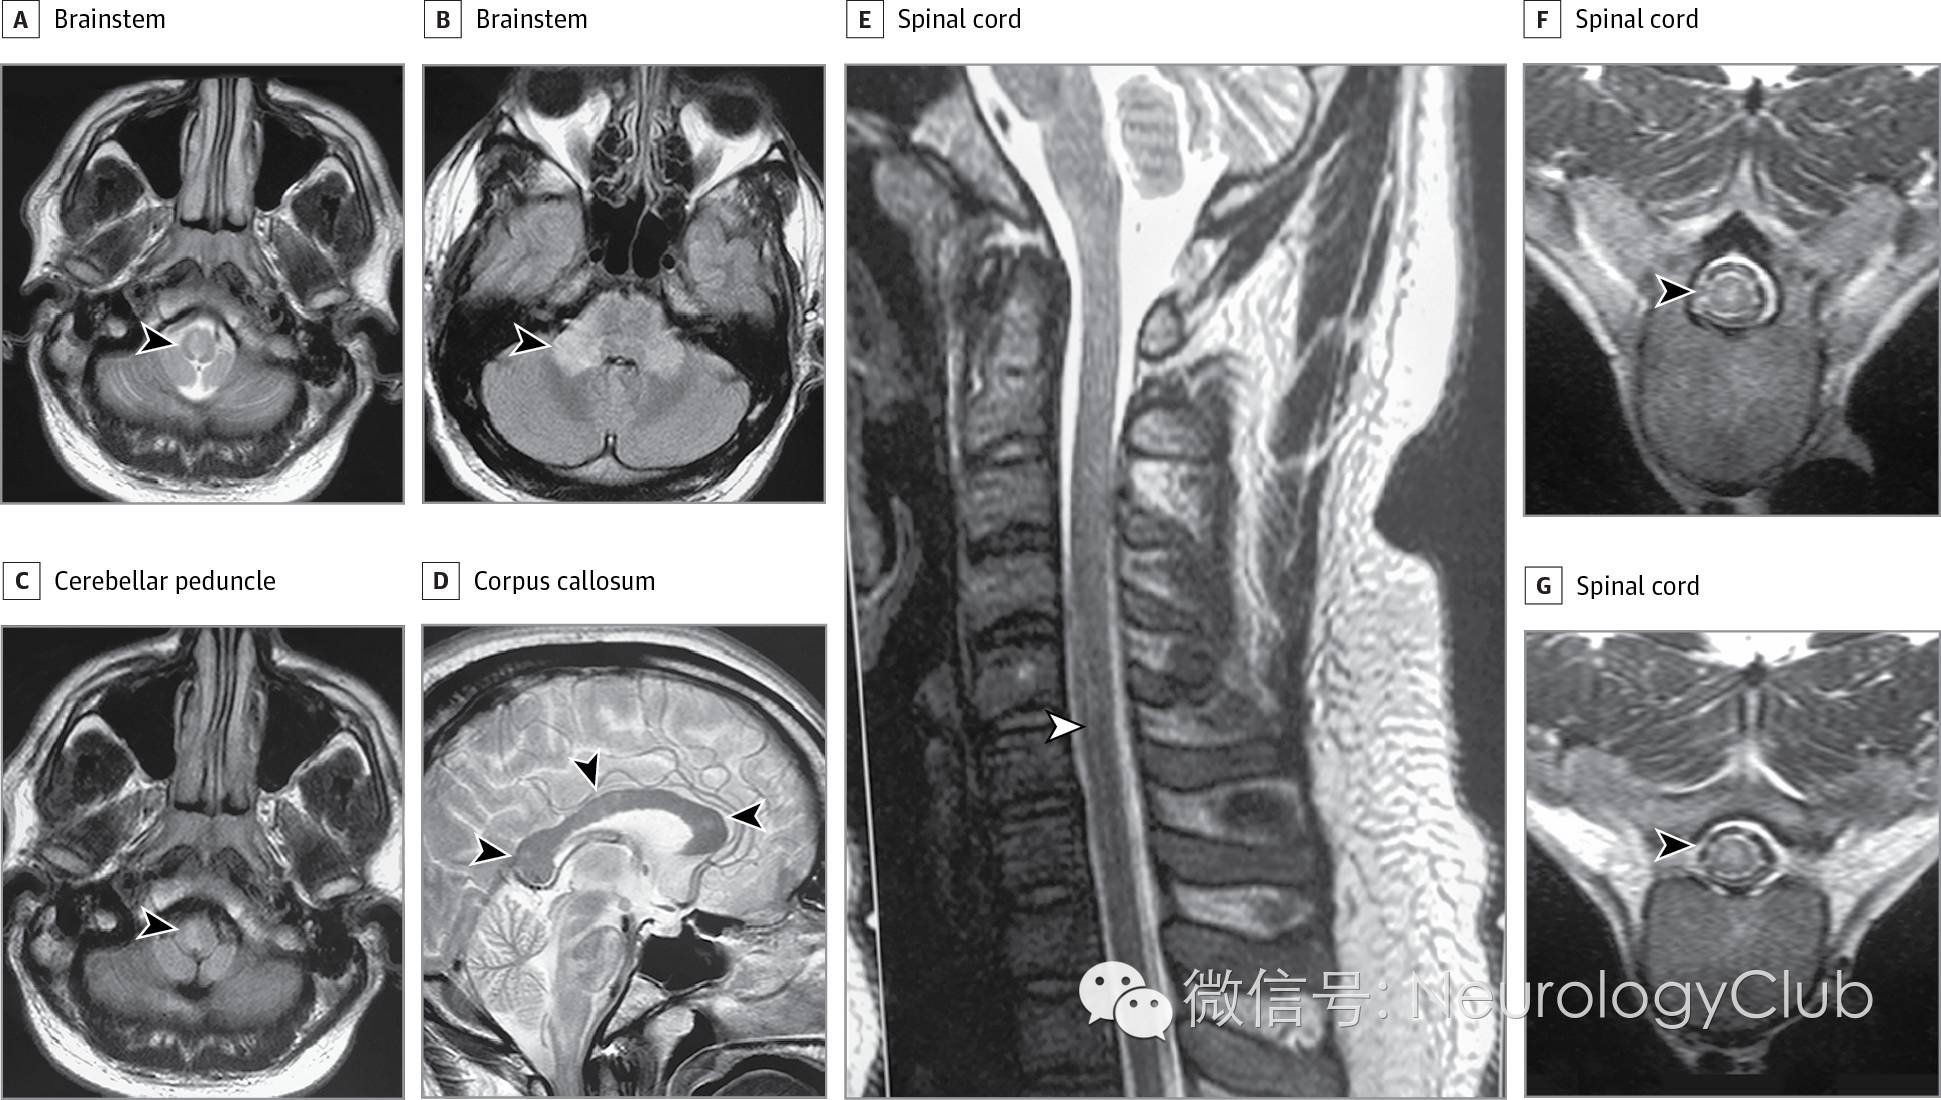

20余岁男性,因临床脱髓鞘综合征至多发性硬化中心就诊。2周前患者确诊为登革热。连续5天患者均有高热和皮疹。血液学检查提示血小板减少症(血小板70×10^9/L),登革热IgM阳性。患者从病毒感染中逐渐康复,但10天后出现复视,视神经炎,下肢轻瘫,浅感觉和本体感觉异常以及反射亢进,尿失禁,眩晕和共济失调步态。患者出现卧床不起,意识模糊,并有过度睡眠。头颅和脊髓MRI证实脱髓鞘的存在(图)。

(图:MRI提示脑干,小脑脚,胼胝体和脊髓[C3-C6椎体]脱髓鞘病变[箭头])